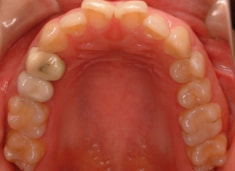

治療開始から1年7ヶ月後